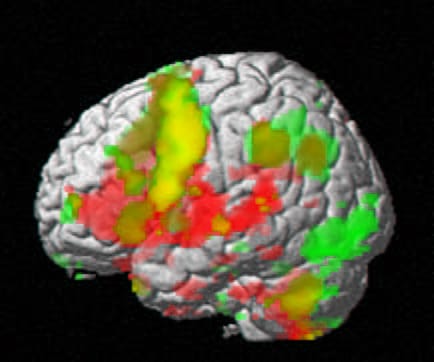

La Neurociencia parece dar la razón a esta ambigüedad entre lo físico y lo emocional: la llamada «neuromatriz del dolor» (un conjunto de areas cerebrales que se activan cuando sentimos dolor) también lo hace si nos sentimos excluidos socialmente. El dolor corporal y anímico utilizan la misma matriz de conectividad para expresarse.

Hay autores (Ianetti) que cuestionan que la neuromatriz del dolor sea una neuromatriz del dolor. Más bien la consideran como un sustrato de conectividad de «lo relevante negativo». Tanto si la relevancia es física («perturbación física de la morada») como si es anímica, el cerebro proyecta esa vivencia desagradable, triste, preocupante que nos incita a una reflexión analítica de sucesos causales negativos potenciales y una búsqueda de acciones que nos libren del afligimiento. Para ello activa la matriz del sufrimiento coloreándola con cualidades perceptivas específicas según los contenidos de lo evaluado como diana de la relevancia. Si considera relevancia de daño físico potencial: dolor; si la relevancia es de posible desnutrición, hambre; si deshidratación:sed; si exclusión social: soledad…